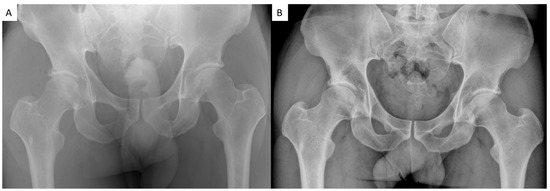

Subchondral Phosphate Injection During Hip Arthroscopy Safely Treats Acetabular Bone Marrow Lesions in Early Osteoarthritis

by Marco Minelli, Berardo Di Matteo, Vincenzo Longobardi, Alessio D’Addona, Marco Rosolani, Sebiano Pitronaci, Elizaveta Kon and Federico Della Rocca

J. Clin. Med. 2025, 14(23), 8298; https://doi.org/10.3390/jcm14238298 - 22 Nov 2025

Introduction: Arthroscopy for femoroacetabular impingement (FAI) yields inferior outcomes when subchondral edema and cystic degeneration are present. Subchondroplasty (SCP), which involves injecting osteoconductive calcium phosphate into Bone Marrow Lesions (BMLs), may enhance subchondral structural support and can be performed alongside hip arthroscopy. [...] Read more.

Introduction: Arthroscopy for femoroacetabular impingement (FAI) yields inferior outcomes when subchondral edema and cystic degeneration are present. Subchondroplasty (SCP), which involves injecting osteoconductive calcium phosphate into Bone Marrow Lesions (BMLs), may enhance subchondral structural support and can be performed alongside hip arthroscopy. Materials and Methods: This single-center retrospective study included patients who underwent SCP for acetabular BMLs during primary hip arthroscopy for FAI from March 2019 to March 2023. Clinical and radiographic outcomes were recorded at ≥2-year follow-up. Survivorship with treatment failure as the endpoint was assessed using Kaplan–Meier analysis. Results: Thirty-four patients were evaluated at a mean 3.1-year follow-up. No perioperative, early, or late complications or adverse events occurred. No bone substitute migration or intra-articular extravasation was seen. Four patients (11.8%) showed osteoarthritis progression and required conversion to total hip arthroplasty; no intraoperative issues with acetabular preparation were encountered. All clinical scores improved significantly (p < 0.001), and 82.4% returned to sport. Conclusions: SCP performed during hip arthroscopy appears safe in selected patients with early hip osteoarthritis and BMLs. Calcium phosphate injection may help restore subchondral integrity and load distribution, though the independent contribution of SCP beyond standard arthroscopic management remains uncertain. Full article

Show Figures

Figure 1